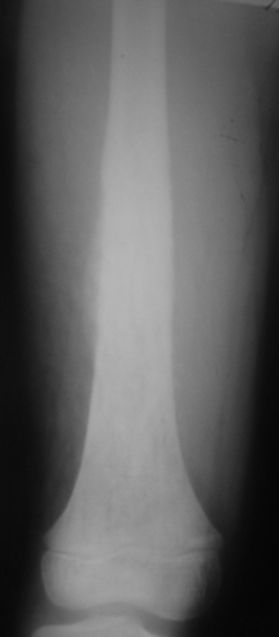

Мальчик 8 лет. Жалобы на боли в левом бедре. Со слов мальчика, ударился бедром несколько

недель назад, после чего и начались боли.

В общем-то, диагноз сомнения не вызывает злокачественная опухоль, вероятнее всего -

остеогенная саркома. У нас возникла дискуссия по поводу того, нужно ли брать открытую

биопсию для гистологического подтверждения диагноза, либо сразу направить ребёнка в

специализированный центр. С одной стороны, диагноз должен быть подтверждён

гистологически. С другой - каждое нерадикальное вмешетельство на опухоли увеличивает

вероятность метастазирования. В литературе чаще встречается такой подход - пациента сразу

направляют в специализированный центр, где ему проводят как биопсию, так и дальнейшее

лечение. Хотелось бы узнать мнение уважаемых коллег.